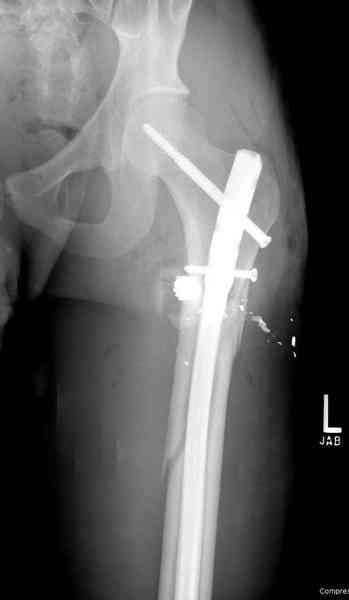

В нашем случае 21 летний боец уличного фронта, фиксацию провели на следующий день, зафиксирован интрамедуллярным штифтом. Не стали делать первичную хирургическую обработку точечной раны, зафиксирован как есть. Клинические снимки:

Конечно, наш случай не эталон, возможно, на месте вам виднее, может быть, нет необходимости ориентироваться на зарубежные ссылки, если получается лечить аппаратом Илизарова на месте, почему нет? Необходимо посмотреть собственный арсенал, чем фиксировать, и какая теория, иначе любой отличный метод можно превратить в источник остеомиелита.

Сам скептически отношусь к тому, когда говорят что одного взгляда достаточно, чтобы сделать такой случай у себя. Без спешки примите решение, возможно, еще не время, и, наверное, будет разумным поехать к тому у кого большой опыт.